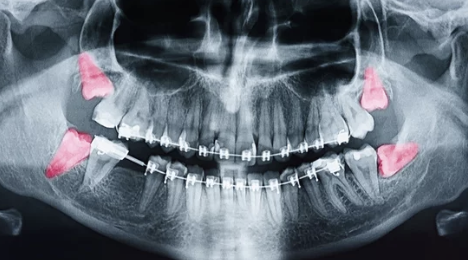

- 치과 상담: X-ray 촬영으로 사랑니의 위치, 매복 상태, 주변 신경과의 관계를 확인합니다.

- 진단: 사랑니의 발치 필요성을 결정하고 발치 방법(일반 발치, 수술적 발치)을 계획합니다.